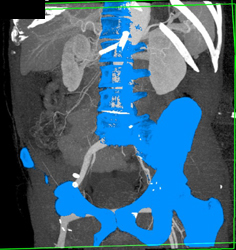

Aortic Dissection